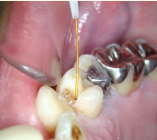

エンドシステム

歯の根の治療は基本的な治療ですがとても複雑。

専用機器を使ったシステマチックな治療で効率良い処置を行っています。

- エンドシステム

- エンドシステム治療